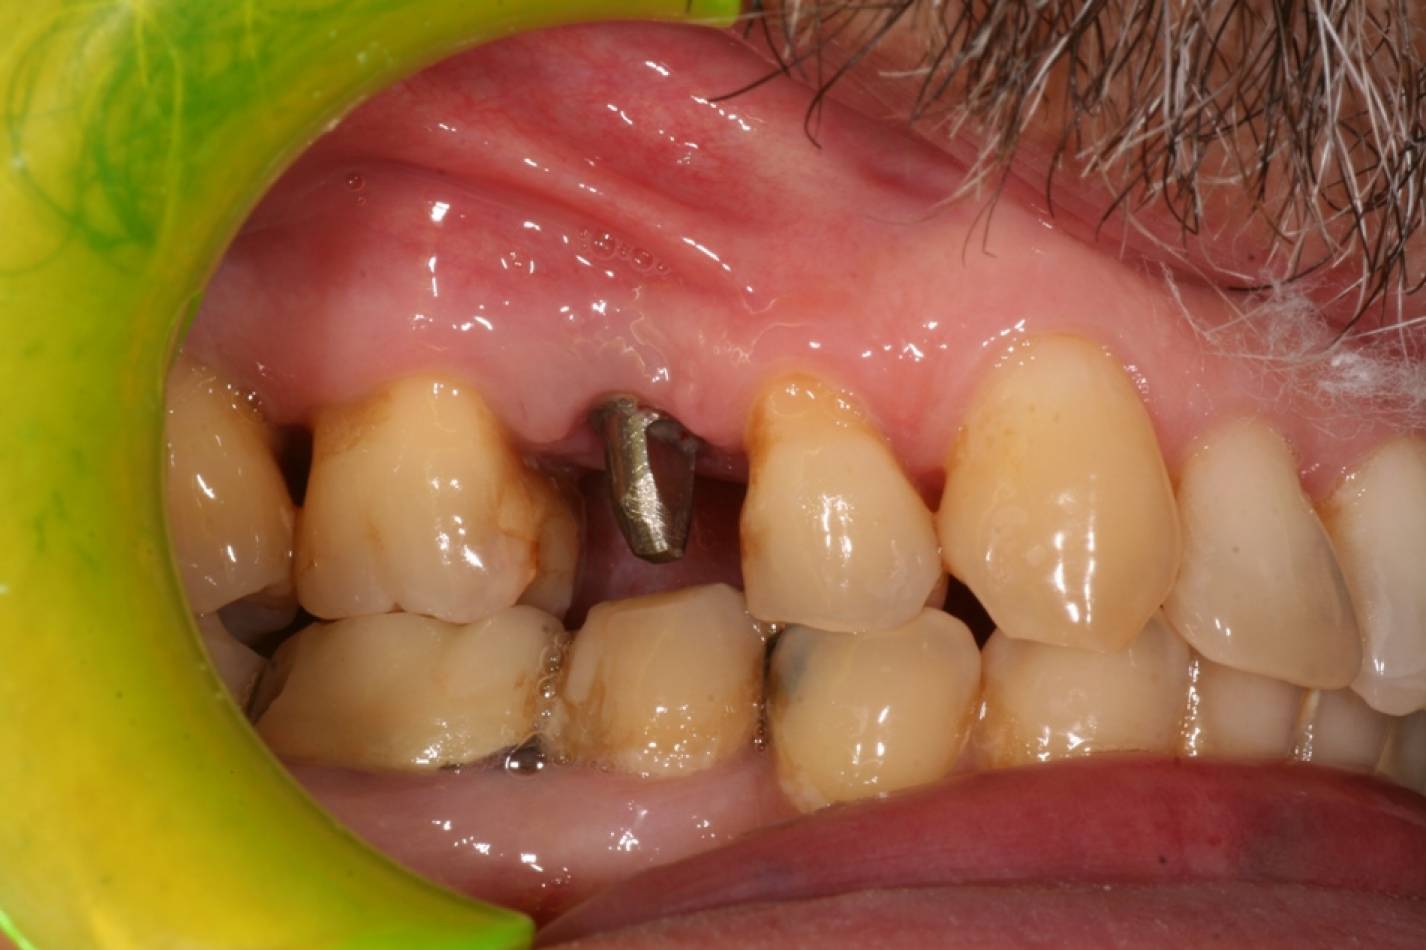

Si effettua implantologia con impianti STRAUMANN e tecnologia IDI EVOLUTION.